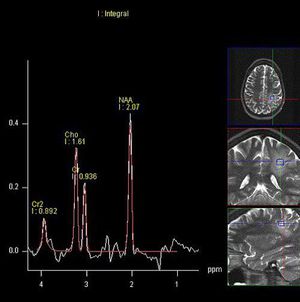

The main purpose of #proton_MR_spectroscopy is to obtain the concentration of major metabolites in the body while MR imaging is used to obtain morphological and functional information in the body. #MR_spectroscopy shows a spectrum graph, which is proportional to the concentration of metabolites, while MR images show a signal proportional to water content and relaxation properties of the tissues and lesions in the brain. #MRS can be used to visualize NAA (neuron activity marker), choline (cell membrane marker), creatine (energy metabolism), lipids (product of brain destruction), lactate (product of anaerobic glycolysis), myoinositol (glial cell marker, osmolyte hormone receptor), glutamine, and GABA (neurotransmitters). Alanine and few other metabolites can be visualized in different disease states as well. MRS graphs show the metabolite’s spectral location in ppm (parts per million). This is essentially an indication of how far apart they are from the resonance frequency (chemical shift). #MR_spectroscopy #SVS #single_voxel_spectroscopy #MRI